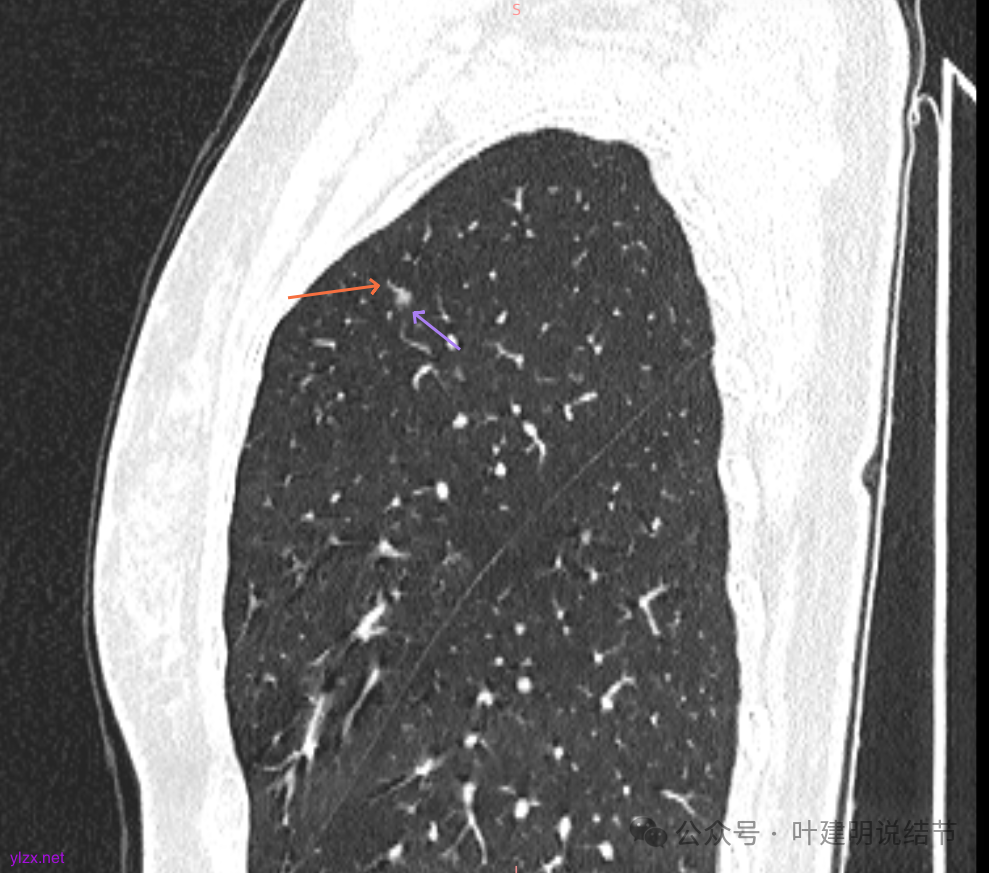

主病灶矢状位有血管进入,边缘毛糙,密度不纯,倒是更像肿瘤些。

两肺多发磨玻璃结节,我们主要看最主要的病灶有没有风险或者有没有进展就可以。我是先看2025年的,黄色的微小磨玻璃结节,密度很低,但是轮廓较为清楚,需要考虑肺泡上皮增生或者肺泡间隔增宽,严格意义上应该没有算肺癌,但是以后有可能会发展到不典型增生或者原位癌,当然也可能永远发展不到那个程度,所以目前不需要管;蓝色的到底是肺泡上皮增生还是少许慢性炎不太好确定,因为轮廓稍显模糊,但它又是磨玻璃密度,总归近期是能够随访的;橘色的密度比黄色的略高,有可能会使肺泡上皮增生或者不典型增生,目前也仍可以随访;粉色的是主病灶,位于左肺上叶,混合密度,表面毛糙,由小血管进入,单次看需要考虑微浸润性腺癌可能性较大。然后我们再来看2020年的影像,因为除了粉色的其他的都没有风险,所以不需要一一去找出来,重点关注粉色这处当时是怎样的。我们发现这个病灶5年前就有,也有小血管进入,也有表面毛糙,也是磨玻璃密度,但是当时磨玻璃当中没有实性的成分,是纯磨玻璃伴微小血管进入。对比起来看,这个病灶在5年当中略有进展,原来应该是腺体前驱病变,现在应该是原位癌或者微浸润性腺癌。那么是不是现在就到了一定得马上手术的程度呢?这个仍然可能是不同医生意见会有出入的。假如说从再随访是不是马上会转移来讲,这么小的肿瘤,发展这么慢,而且仍然含有磨玻璃成分,病理考虑与微浸润性腺癌可能性较大,应该仍然不至于说没有随访的空间。但是如果继续随反思想压力比较大,以及即便在随访后续仍然总得要开刀来说,加上病灶位置靠胸膜并不远,简单的单孔胸腔镜楔形切除就能解决问题,将有一定风险的这个病灶切了,同样是可行的。这需要你自己权衡决定。我没有办法100%给十分确切的意见。但是如果从倾向性来讲,由于是多发病灶,加上年纪还轻,风险还不是很大,稍微清一下雨6~9个月复查,有进展病风险再增加再考虑手术。意见供你参考!